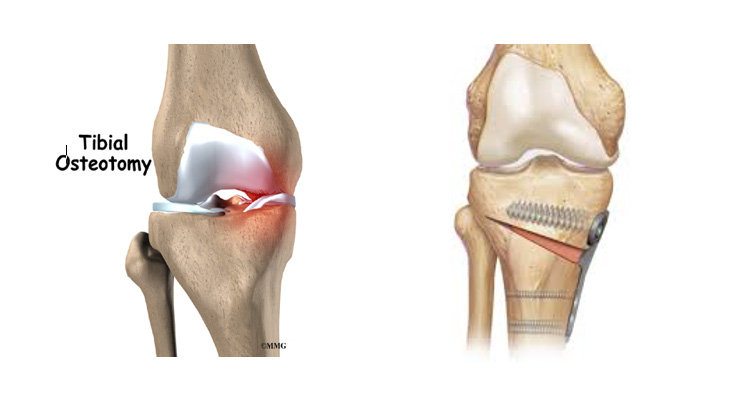

Osteotomy:

Image Source: https://drlingarajuortho.com/high-tibial-osteotomy/

This procedure involves removing and realigning the bone to relieve the pressure on the joint or bone.